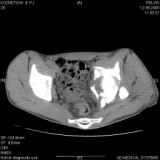

Повреждение вертлужной впадины 2,5 мес. |

Уважаемые коллеги! Хотелось бы услышать совет по тактике лечения представлленого больного.Поступил после лечения в одном изотделений области. Травма 2,5 месяца назад. После выведенияиз шока был произведен остеосинтез перелома бедра, предплечья, до перевода к нам проводилосьвытяжение по оси шейки бедра за стержень, введенный в большой вертел. На сегодня деформацияригидна, клинически мобильности не определяется. Заранее признателен. P.S. Данный вид травм не включен в перечень "высокотехнологичных операций", направить длялечения по квотам Минздрава очень сложно.

Это обзорные и косые снимки

Привет, Леонид. Оскольчатый высокий двухколонный перелом в такие сроки трогать не надо, т.к. это про такие переломы сказано: "кто с ножом на Ж. пойдет тот в ней и останется...".